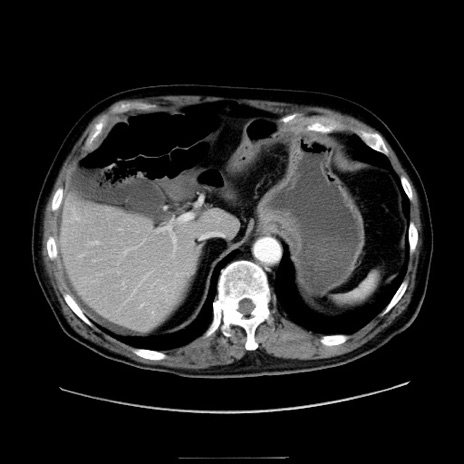

冠状断像

【症例】80歳代男性

【主訴】臍周囲痛

【現病歴】約6時間前から臍下部痛が出現。次第に腹部膨隆・背部痛も生じてきたため来院。背部痛の場所は変化しない。

【身体所見】意識清明、BT 36.3℃、BP  131/87mmHg、P 87bpm、SpO2 100%(RA)、臍周囲自発痛・圧痛あり、反跳痛なし、自発痛部位に一致して板状硬あり、腹部膨隆、腸雑音減弱、CVA tenderness両側陰性。

【データ】WBC 19600、CRP 0.33